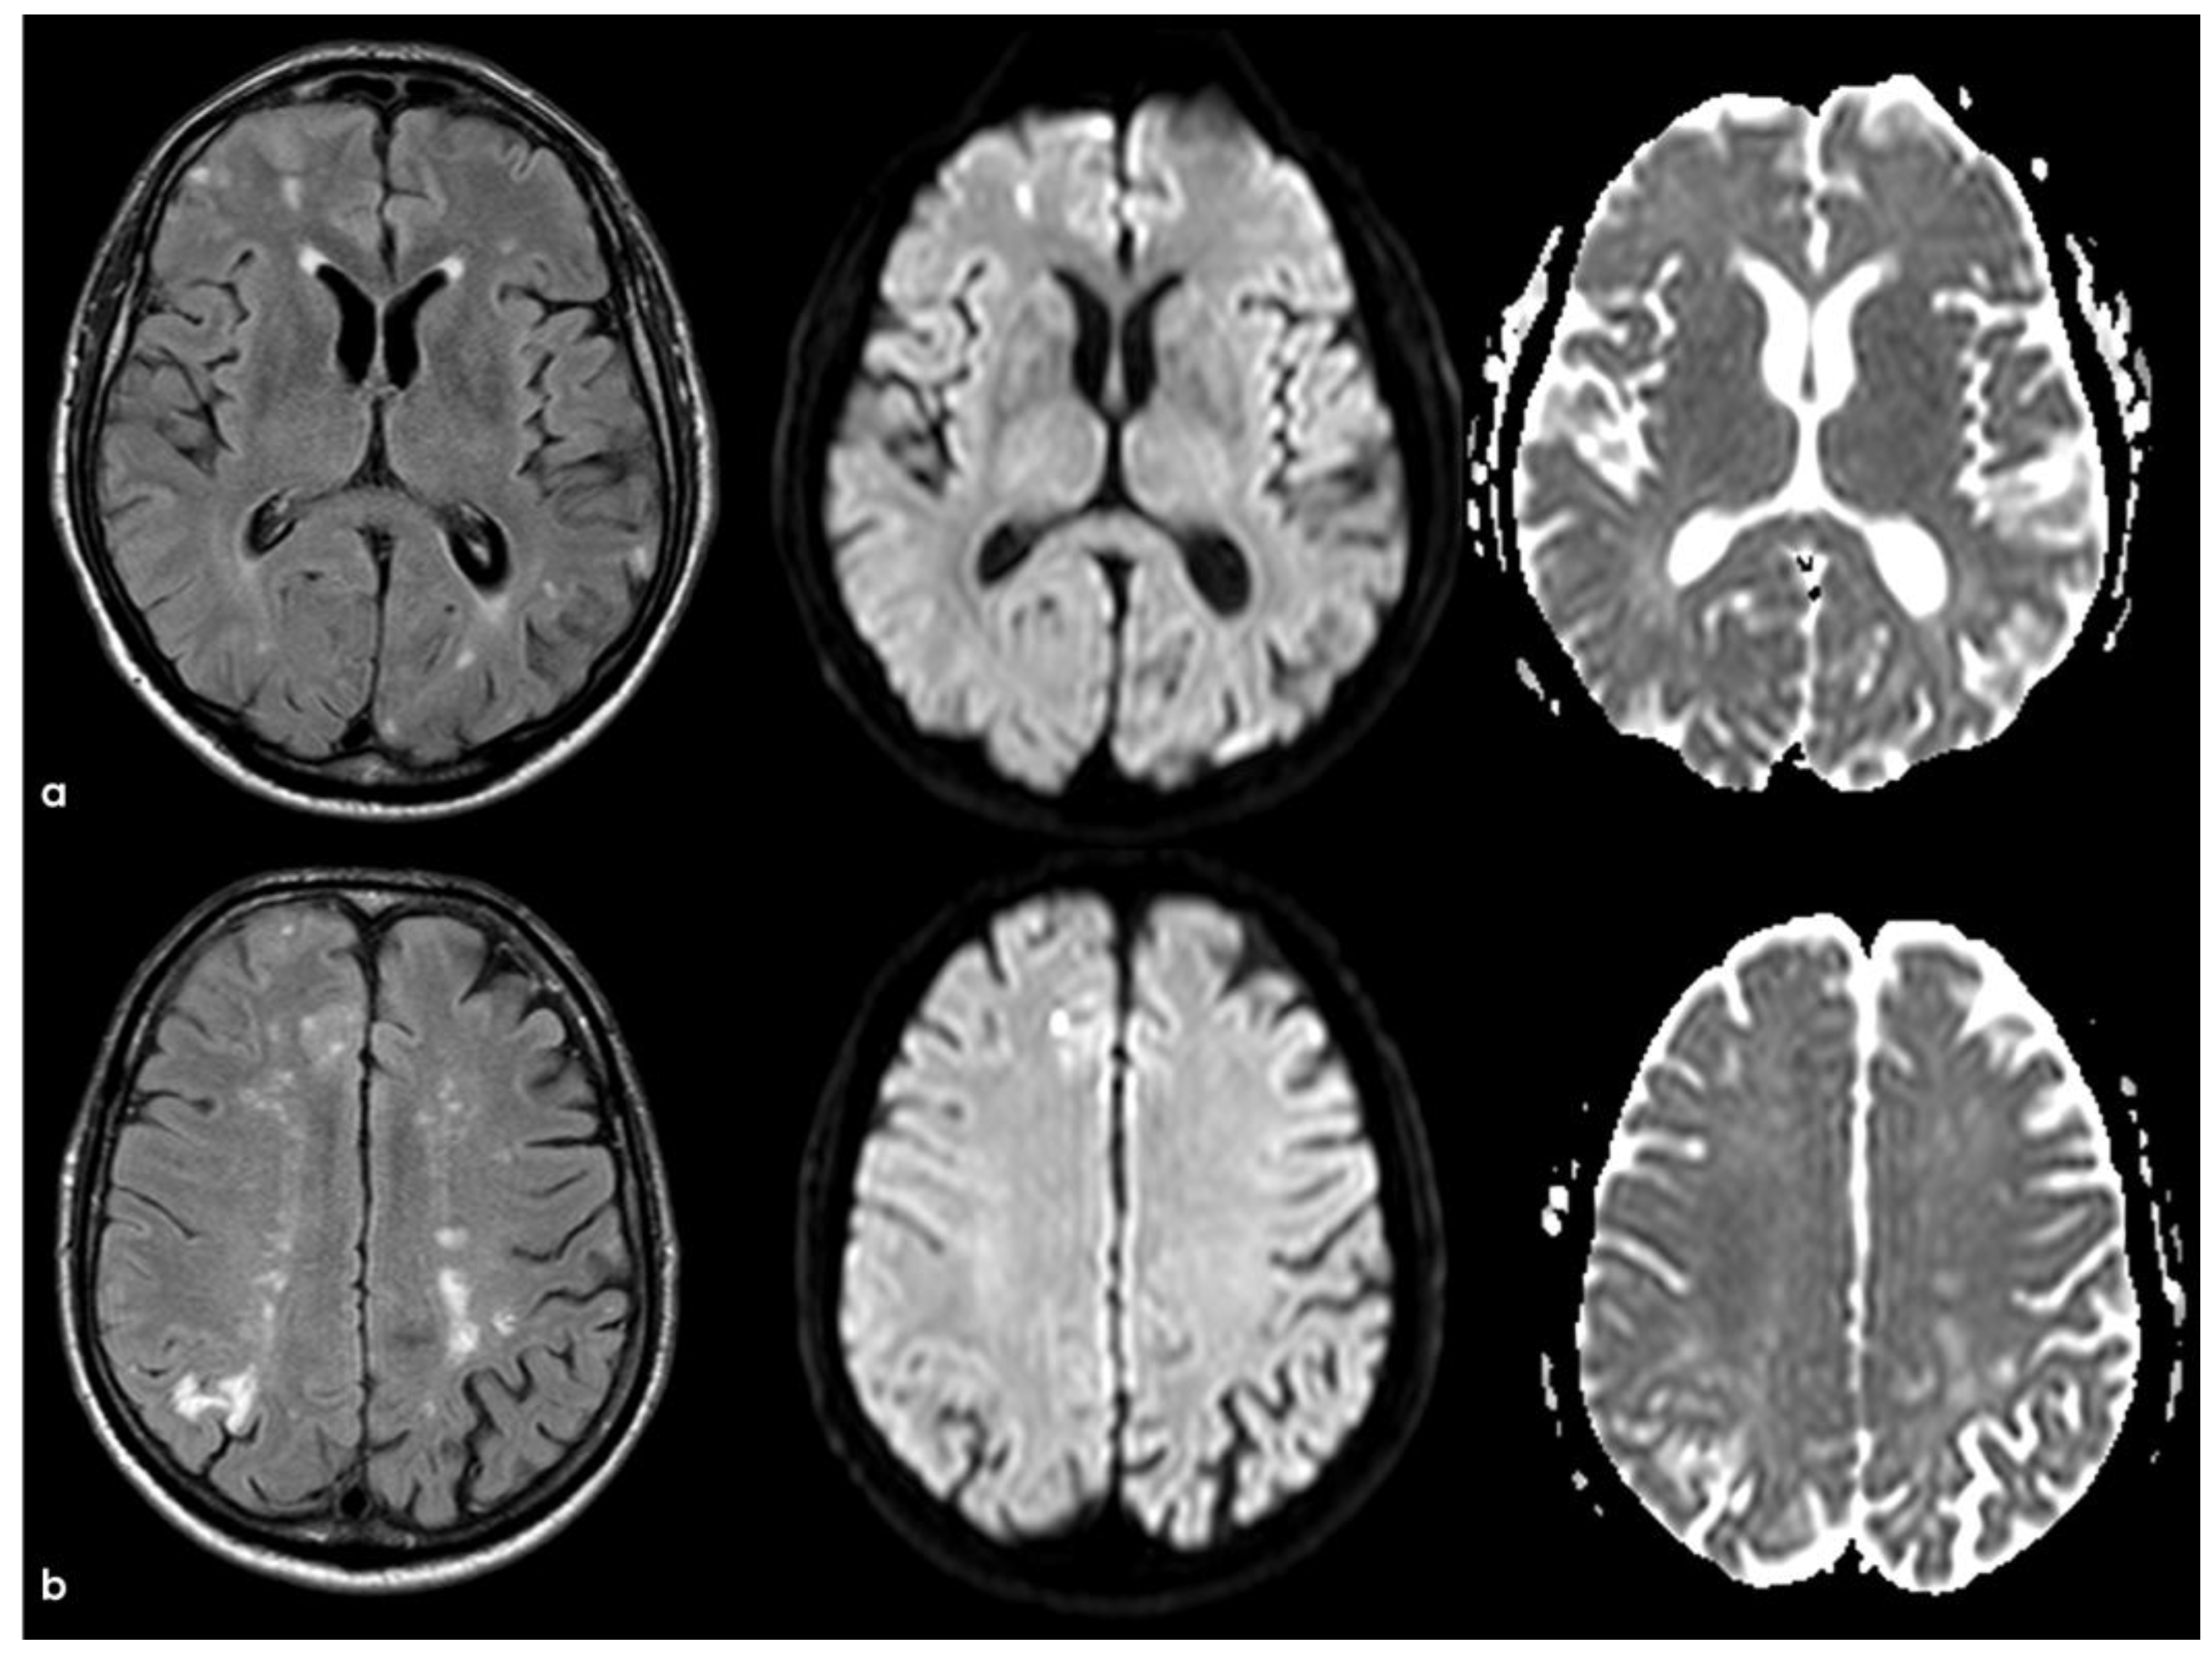

4. December 2015: Ischemic Stroke